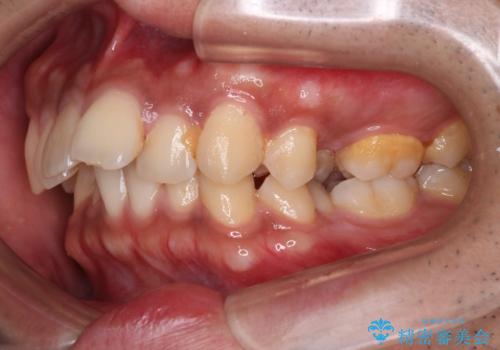

- 歯並びの凸凹を主訴に来院されました。

スペースが必要なため、抜歯を行なって治療を行いました。

奥歯の捻れが強く治療期間がかかりましたが、綺麗な仕上がりに満足していただきました。